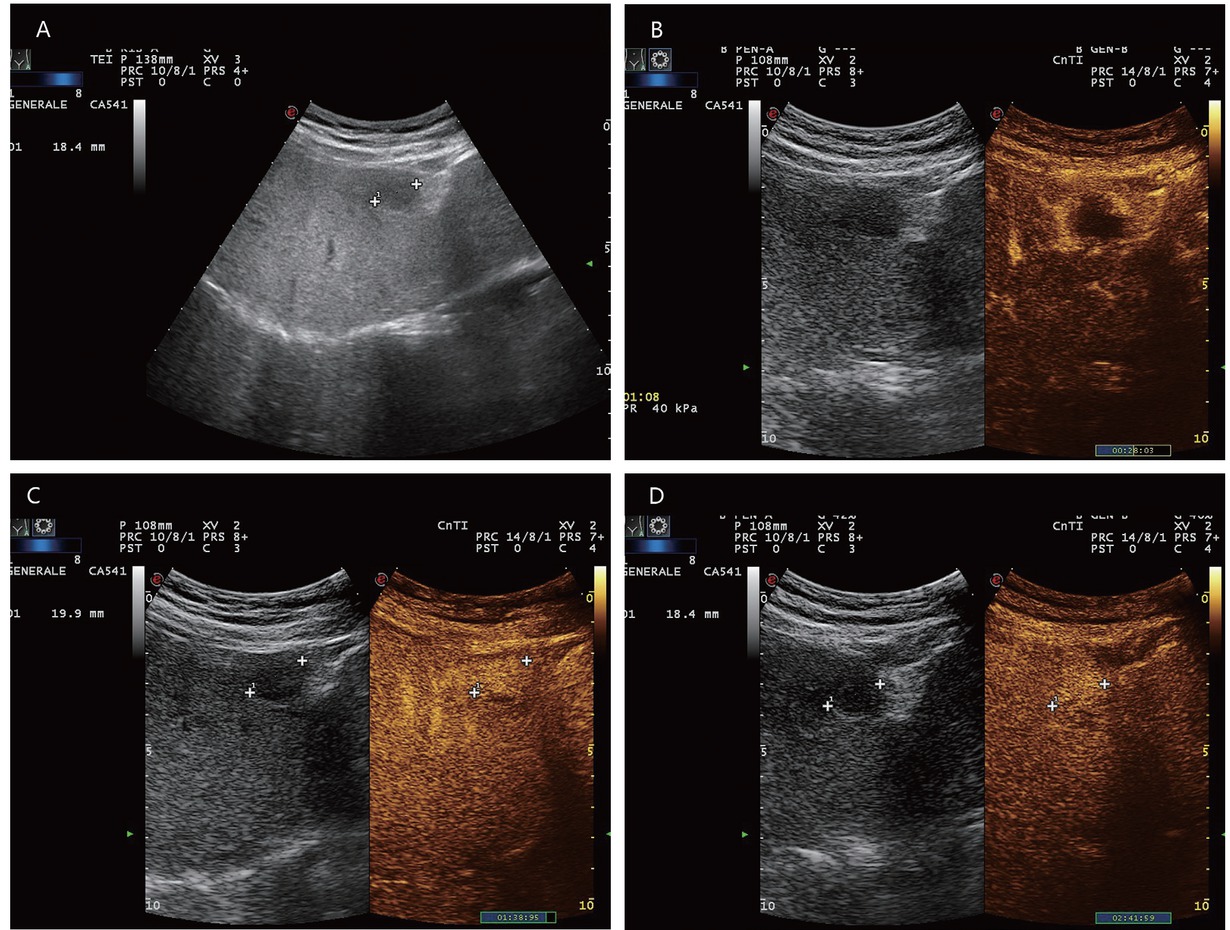

A typical feature of hemangiomas in CEUS is a smooth contrast-receiving ring in the arterial phase with a peripheral, discontinuous nodular (syn.: globular) enhancement with progressive centripetal contrast (Figure 1). The fill-in in the late phase can be complete or incomplete. (Partially) thrombosed hemangiomas do not fill up completely (Figure 2).[9,19]

A 65-year-old male with diabetes and past history of obesity. Hemangioma (in between markers) on the background of steatosis hepatis with severe fibrosis at shear wave elastography (9.5 kPa). Hypoechoic liver lesion in B-mode ultrasonography (A). On CEUS, smooth annular enhancement in the arterial phase (B). Smooth contrast medium lake in the marginal area in the portal venous phase (C). Complete centripetal filling in the late phase (D). Here typical hemangioma. CEUS provides the exact differential diagnostic assignment of a hypoechoic liver lesion in liver cirrhosis and makes further contrast-enhanced radiologic diagnostics unnecessary. CEUS: contrast-enhanced ultrasonography.